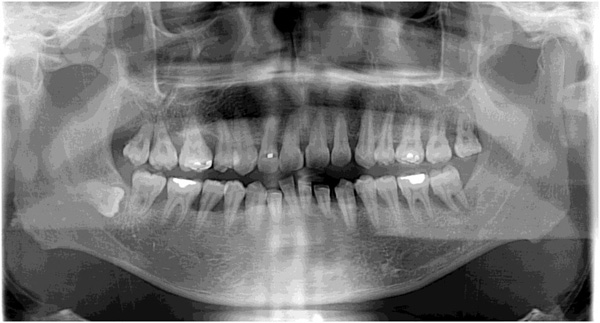

歯周組織検査①

歯周組織検査

歯周ポケットの深さ、骨の形、炎症状態(出血の有無等)歯石の付き具合、歯の動揺度(どのくらい揺れがあるか)などを調べます。

レントゲン撮影